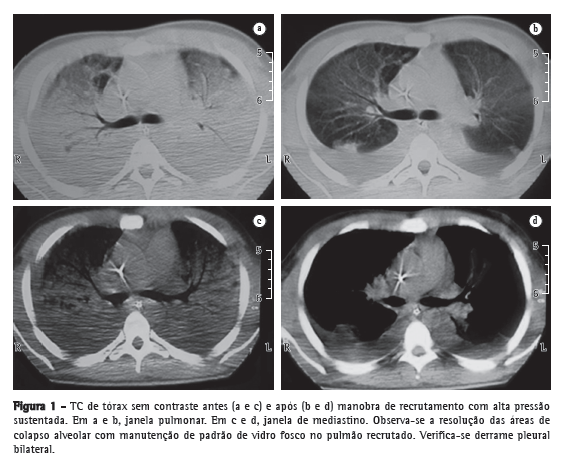

Devido à hipoxemia refratária, o paciente foi submetido à TC e, durante o procedimento, foi submetido a MRA. O paciente foi mantido devidamente sedado e encontrava-se hemodinamicamente estável. Selecionou-se pressure-controlled ventilation (PCV, modo ventilatório controlado a pressão), com FR de 15 ciclos/min, tempo inspiratório de 2 s, relação inspiração:expiração = 1:1, FiO2 = 1, e pressão de 15 cmH2O acima de positive end-expiratory pressure (PEEP, pressão expiratória final positiva) de 25 cmH2O durante 2 min. As respostas funcionais e radiológicas foram avaliadas imediatamente antes de MRA (relação PaO2/FiO2 = 65; PaO2 = 58,9 mmHg; e FiO2 = 0,9) e aproximadamente 20 min após MRA (relação PaO2/FiO2= 102; PaO2 = 71,9 mmHg; e FiO2 = 0,9). As imagens da TC evidenciaram aeração das zonas de colapso alveolar, com persistência de regiões com vidro fosco no pulmão recrutado (Figura 1). Após a MRA, foi realizado o cálculo da PEEP ideal ainda em PCV. A partir de uma PEEP de 25 cmH2O com redução, a cada 2 min, de 2 cmH2O, determinou-se o valor que resultou em maior volume corrente (PEEP: 15 cmH2O) e, portanto, de melhor complacência estática, quando então somou-se 2 cmH2O ao mesmo. Visando garantir a estabilidade do volume corrente e da pressão alveolar optou-se por trocar o modo PCV para volume-controlled ventilation segundo a estratégia ventilatória protetora (volume corrente = 6 mL/kg de peso ideal). A pressão de platô foi monitorada e mantida sempre inferior a 30 cmH2O.